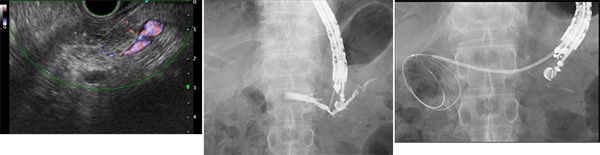

超音波内視鏡(EUS)とは

内視鏡に超音波検査のプローブ(探触子)がついているものを超音波内視鏡(EUS)といいます。エコー検査と違って、胃や腸の中の空気や腹壁、腹腔の脂肪、骨が画像化の障害になることがなく、消化管周囲臓器(膵臓、胆管、胆嚢、リンパ節、粘膜下腫瘍)に対する高い分解能の超音波観察が可能になっています。さらに当科では最新のEUSを導入し、様々な検査や治療を行っております。

超音波内視鏡を使用した手技・検査・治療

超音波内視鏡下での針生検

従来の内視鏡下生検では診断不可能であった膵腫瘍、粘膜下腫瘍、腹腔内リンパ節などを対象に超音波内視鏡で観察しながら針生検を行います。EUS-FNA(超音波内視鏡下穿刺術)と言います。

嚢胞を取り除く(ドレナージ)

超音波内視鏡ガイド下に経消化管的(胃十二指腸から)に嚢胞のドレナージを行います。経皮的(体表から穿刺する)もしくは外科的ドレナージ(開腹手術)に比較し低侵襲で安全に嚢胞ドレナージが可能です。EUS-CD(超音波内視鏡下膵仮性嚢胞ドレナージ)と言います。

胆汁の流出路を作る

何らかの理由で内視鏡的胆道ドレナージが困難な場合に超音波内視鏡ガイド下に胃や十二指腸から胆管を穿刺し、胆汁の流出路を作ります。EUS-BD(超音波内視鏡下胆管ドレナージ)と言います。

膵液の流出路を作る

何らかの理由で内視鏡的膵管ドレナージが困難な場合に超音波内視鏡ガイド下に胃から膵管を穿刺し、膵液の流出路を作ります。EUS-PD(超音波内視鏡下膵管ドレナージ)と言います。